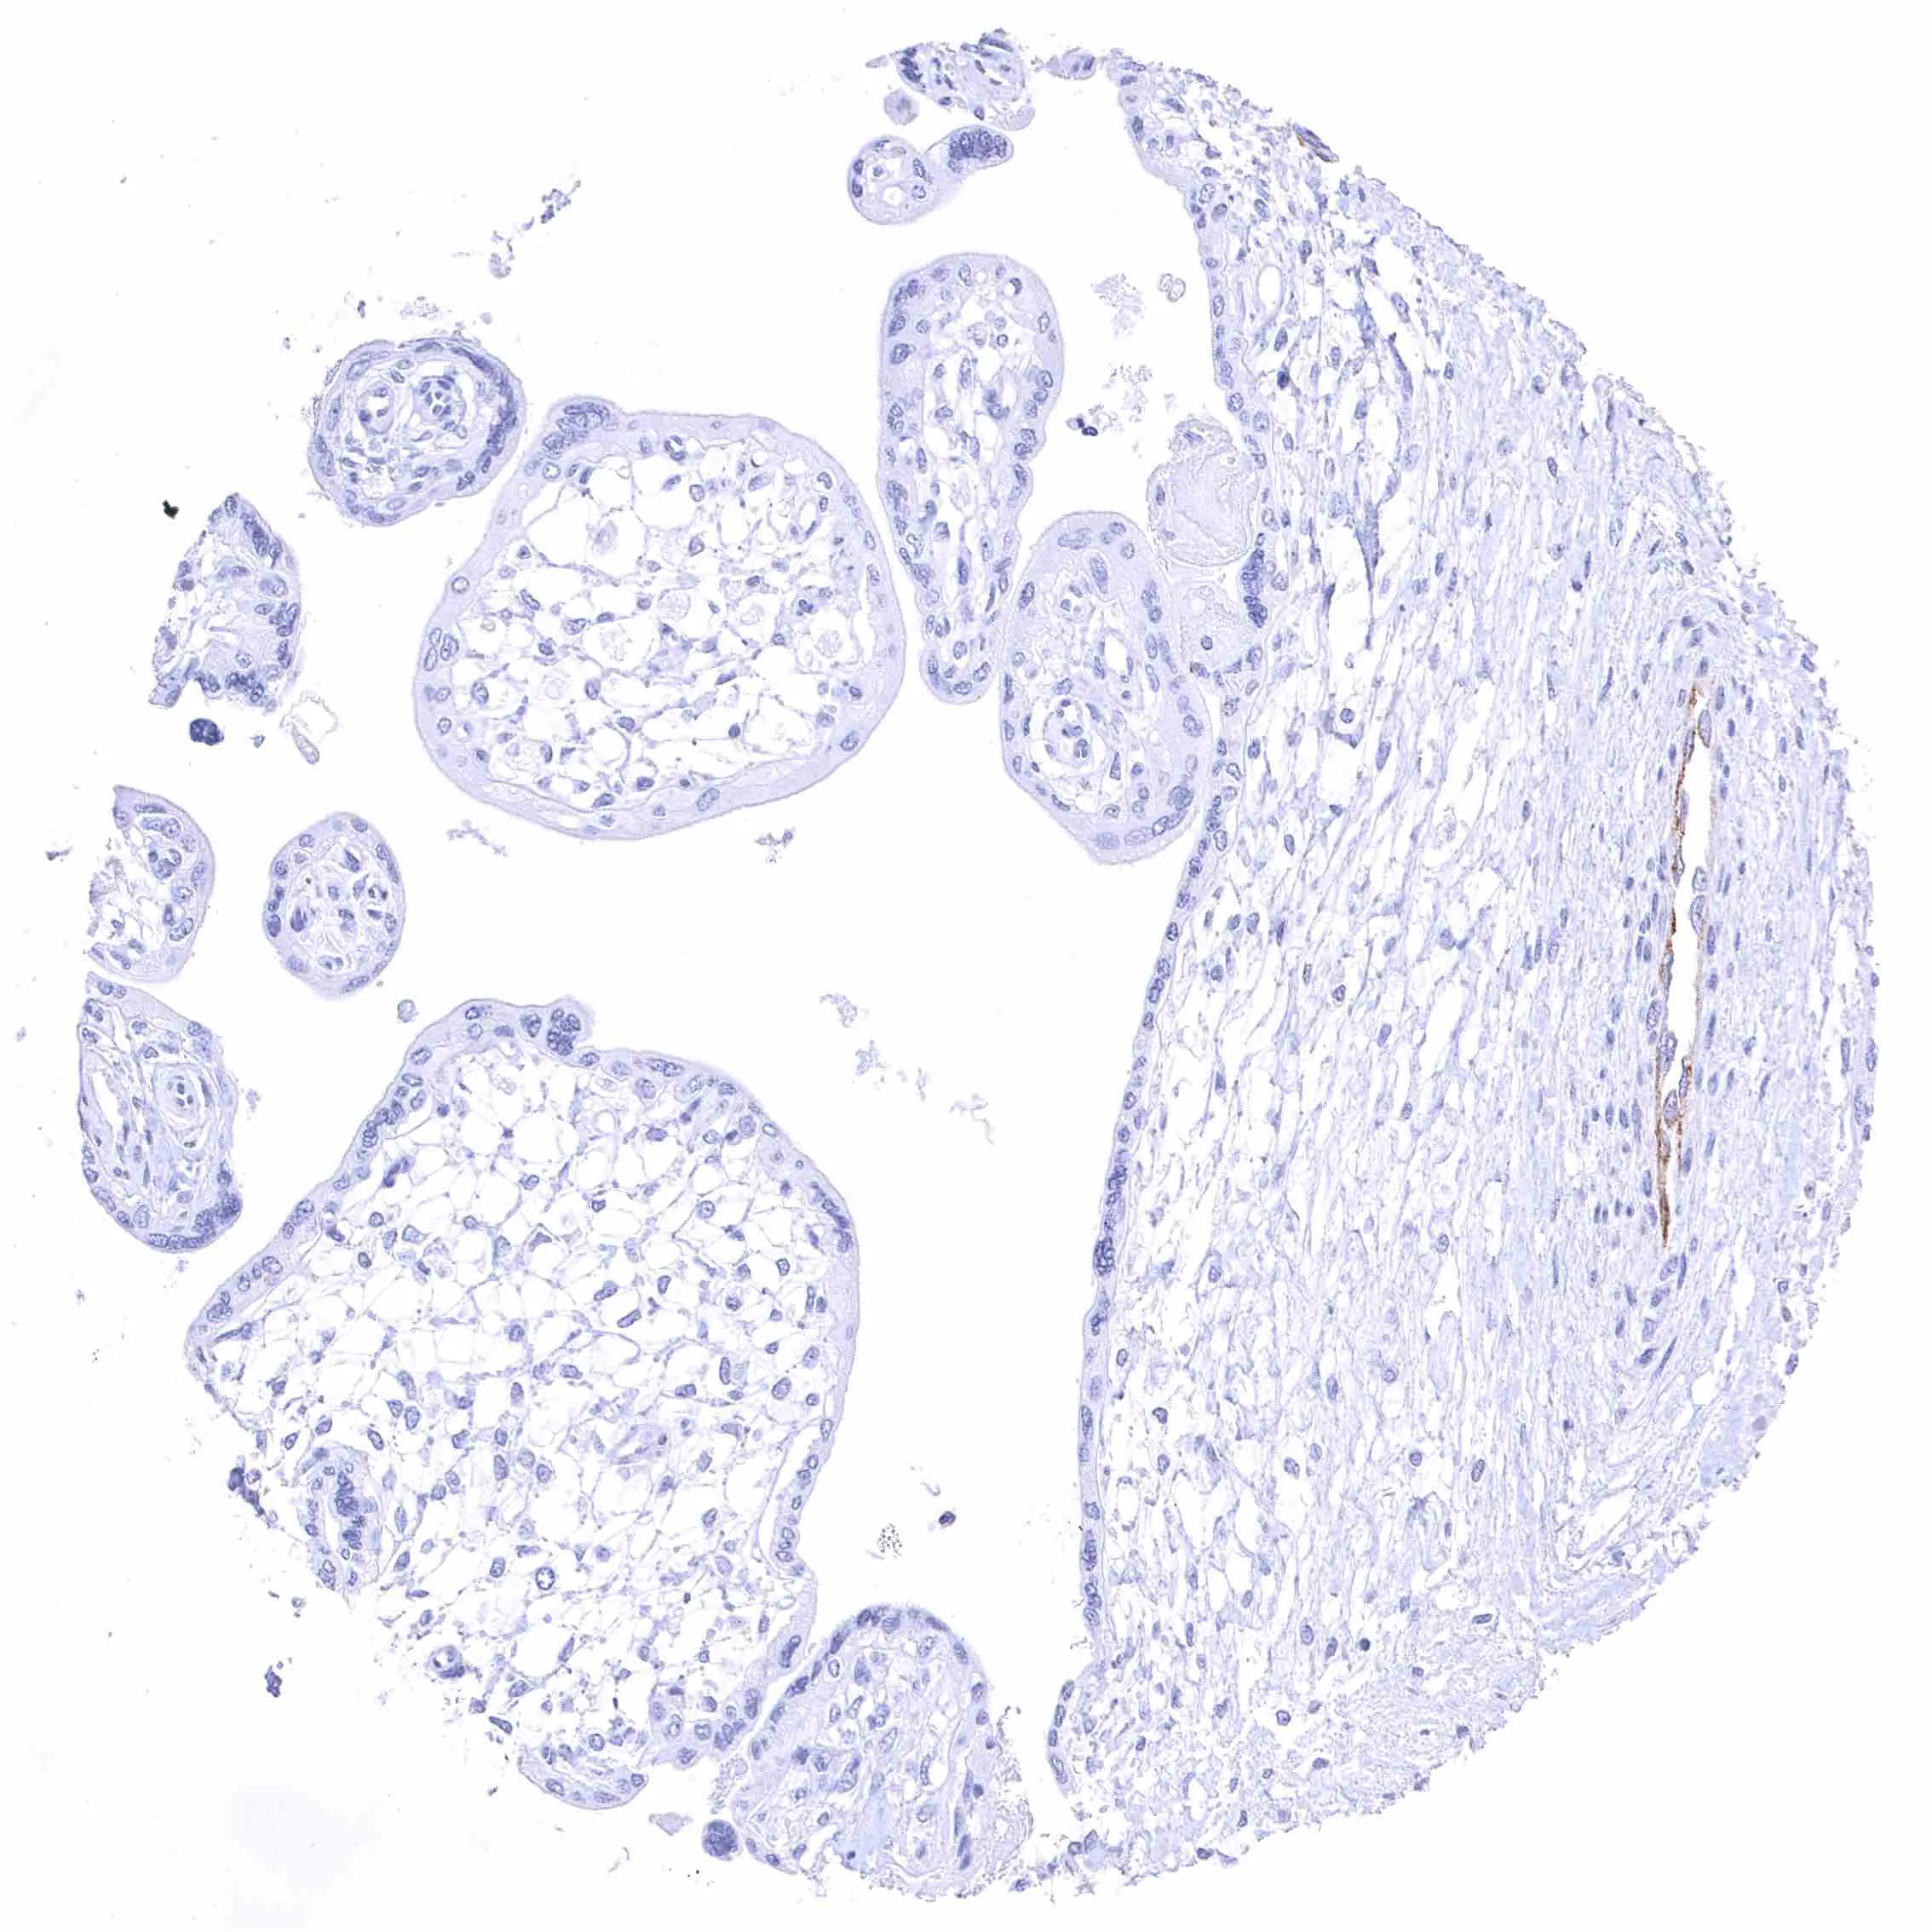

Kidney, cortex – Distinct membranous NPR-C staining at the luminal cell border of a subset of tubuli, the parietal membrane of the Bowman capsule, and in glomerular endothelial cells.

Kidney, cortex – Distinct membranous NPR-C staining at the luminal cell border of a subset of tubuli, the parietal layer of the Bowman capsule, and in glomerular endothelial cells.